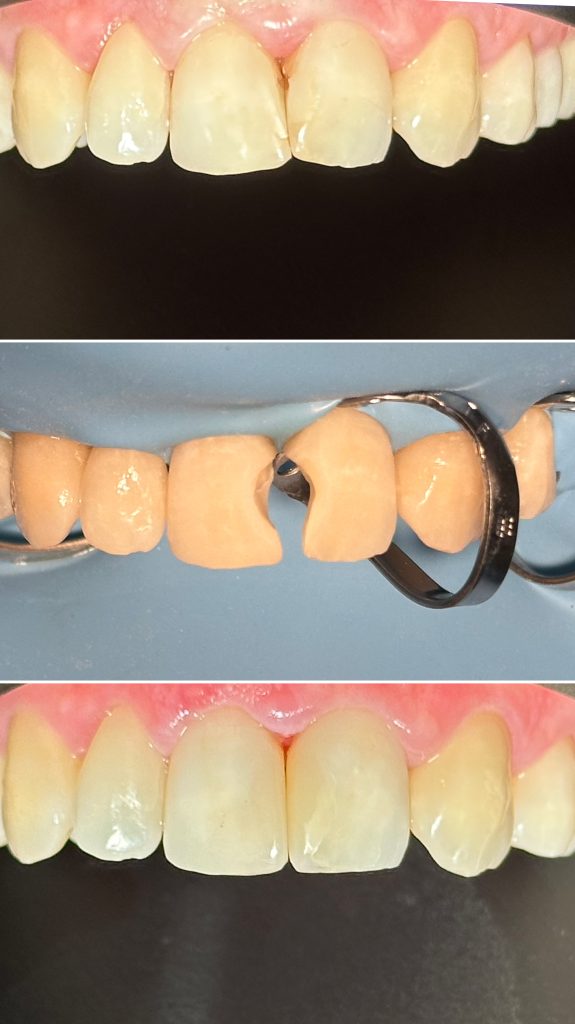

• Художественная реставрация фронтального и бокового участка зубов